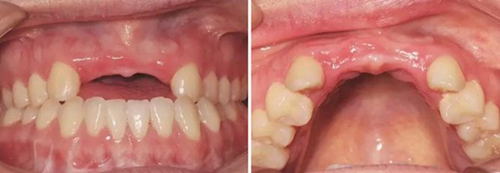

患者,女性,23歲,大學(xué)生?;颊哂?年前因外傷導(dǎo)致上前牙缺失,期間行可摘局部義齒修復(fù),自覺每天摘帶不便,且影響正常發(fā)音及美觀,至我科要求種植修復(fù)。平素體健,無(wú)全身系統(tǒng)性疾病,無(wú)特殊藥物服用史,無(wú)藥物、材料等過敏史,無(wú)吸煙、夜磨牙等不良習(xí)慣??谕鈾z查見口腔頜面部對(duì)稱,張口度正常,中位唇線,中位笑線??趦?nèi)檢查見12、11、21、22缺失,缺牙區(qū)牙槽嵴薄。覆牙合覆蓋淺,23反牙合??谇恍l(wèi)生狀況良好。拍攝CBCT示:12位點(diǎn)可用牙槽骨高度為16.4mm,寬度為3.6mm;22位點(diǎn)可用牙槽骨高度為19.5mm,寬度為3.2mm。

圖1 植骨術(shù)前口內(nèi)正面觀 圖2 植骨術(shù)前口內(nèi)頜面觀